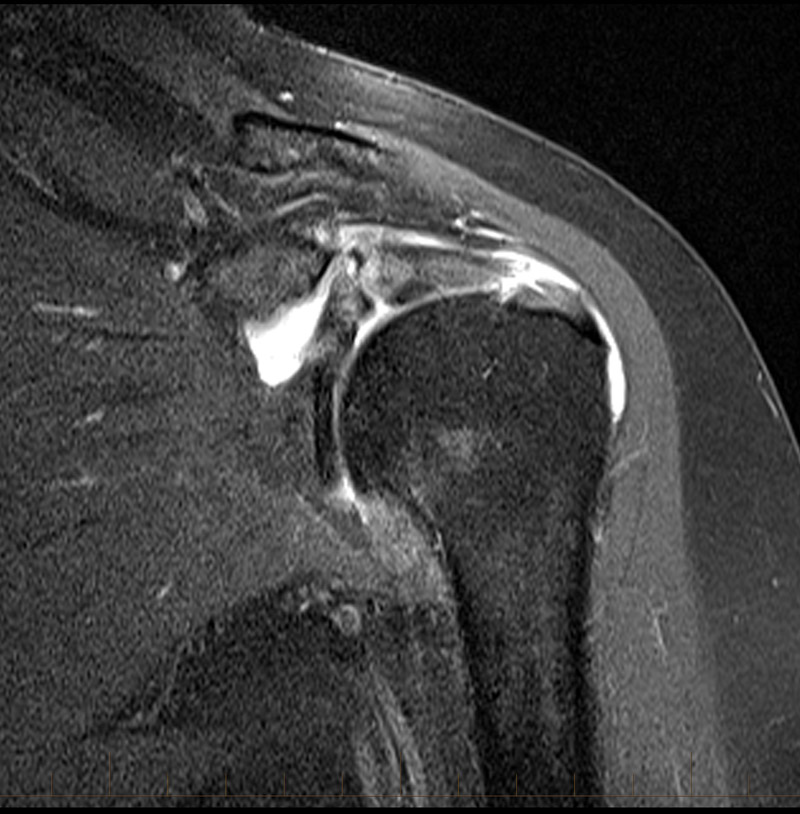

MRI Shoulder – Musculoskeletal Imaging

MRI AP shoulder. Unidad Especializada en Ortopedia y Traumatologia en …